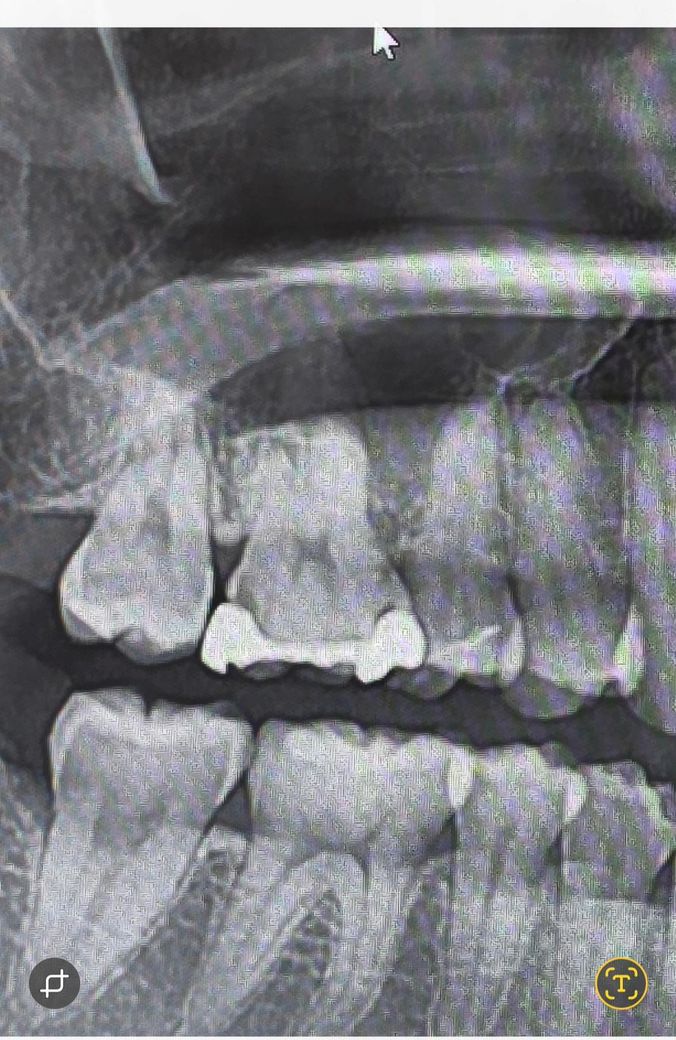

골드인레이 2차충치일까요? 궁금합니다

치과에 갔는데 아무리봐도 충치같은데 괜찮다고 아프면 오라고 하셔서 궁금해 올려봅니다...

통증은 없는거같아요 가끔 잇몸이 아픈거 빼면...

엑스레이상으론 이차충치 맞을 것 같습니다 본딩갭(bonding gap)으로 보기에는 엑스레이상 검은 부분이 다소 뚜렷하네요